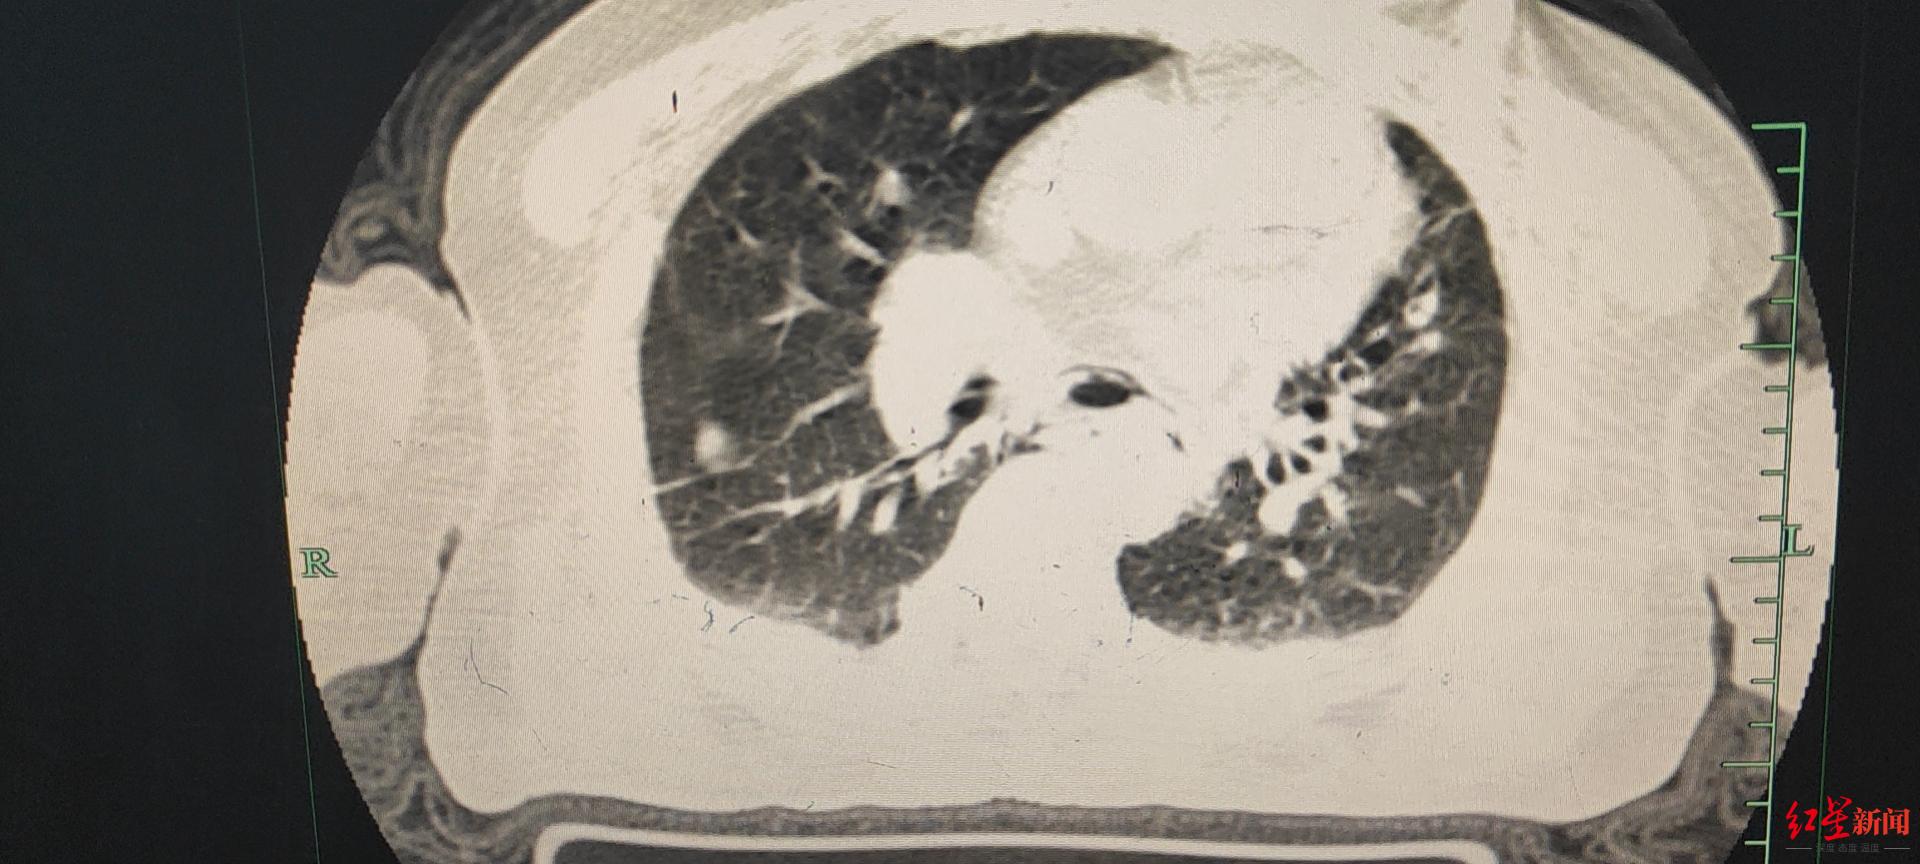

华西医院完成西部首例全胸腔镜下自发性食管破裂修补术